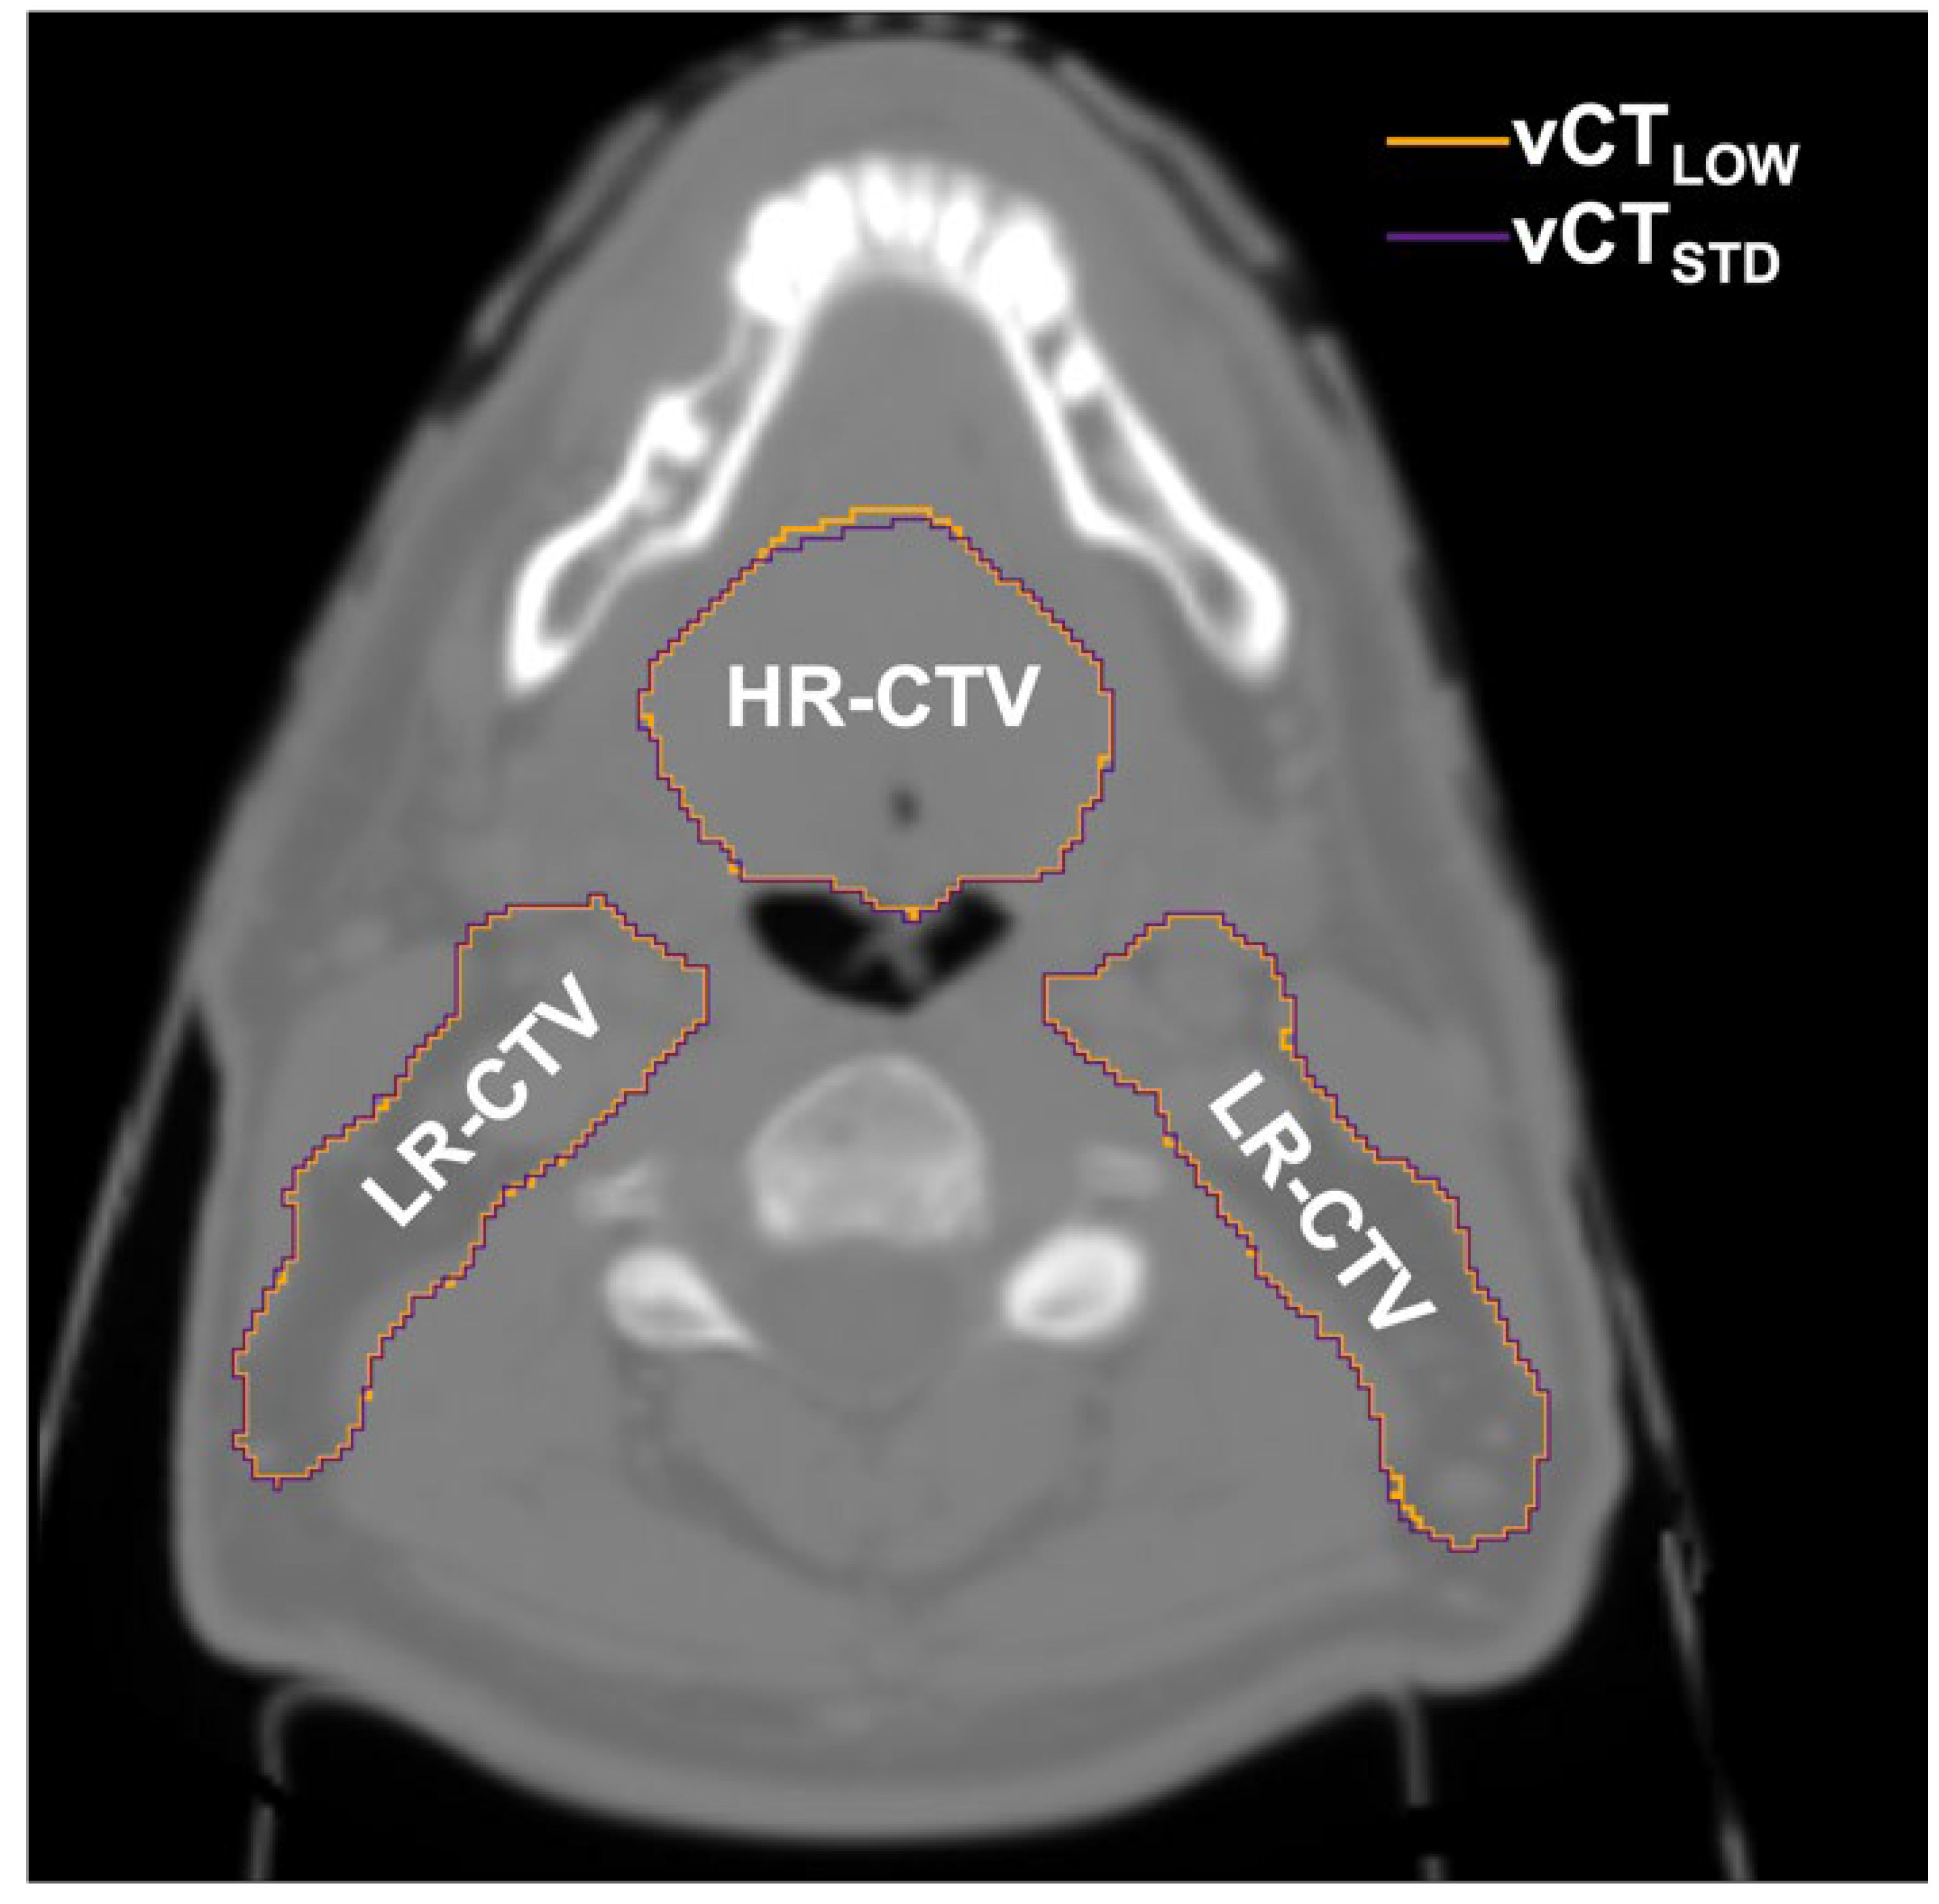

The similarity between contours propagated to low-dose CT and to the reference standard-protocol CT, quantified by the Dice coefficient, is shown in Figure 8 for all low-dose protocols. The Dice coefficient was found to be larger than 0.982 for all the contours in the whole patient cohort, while median values were all above 0.995 for all the protocols studied. As such, no significant influence of image quality on DIR was found. As in the case of DVH metrics, there was also no trend observed with the decrease in image quality. Figure 9 shows the magnitude of the differences between the contours for the target (high-risk and low-risk CTVs). The presented example corresponds to the lowest-dose protocol for a representative patient.

Figure 9.

Difference between contours propagated to the standard-protocol CT (vCTSTD) and the lowest-dose CT (vCTLOW) for the high-risk CTV (HR-CTV) and low-risk CTV (LR-CTV).